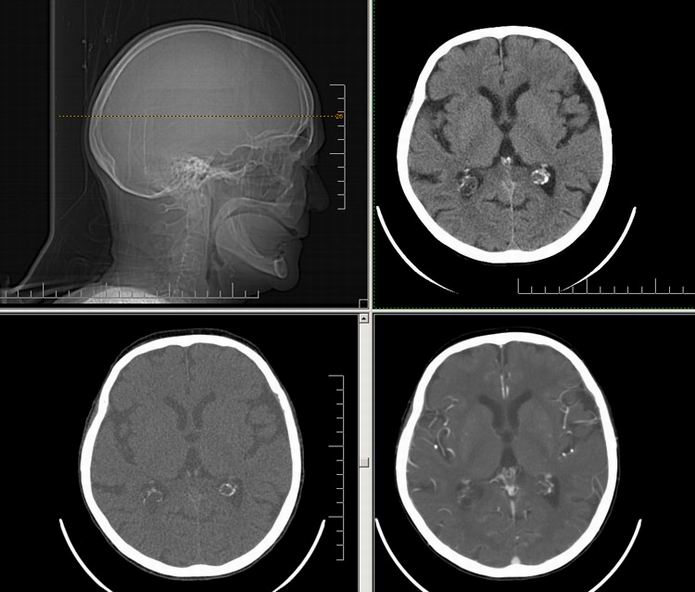

Est ce que qqun a des coupes axiales de crâne pour m'aider à réviser mon anatomie. Merci

Pour compléter tes révisions, Poupette vient de nous faire parvenir ces planches bien utiles: Planches de coupes axiales cérébrales, dans la rubrique COURS / ANATOMIE